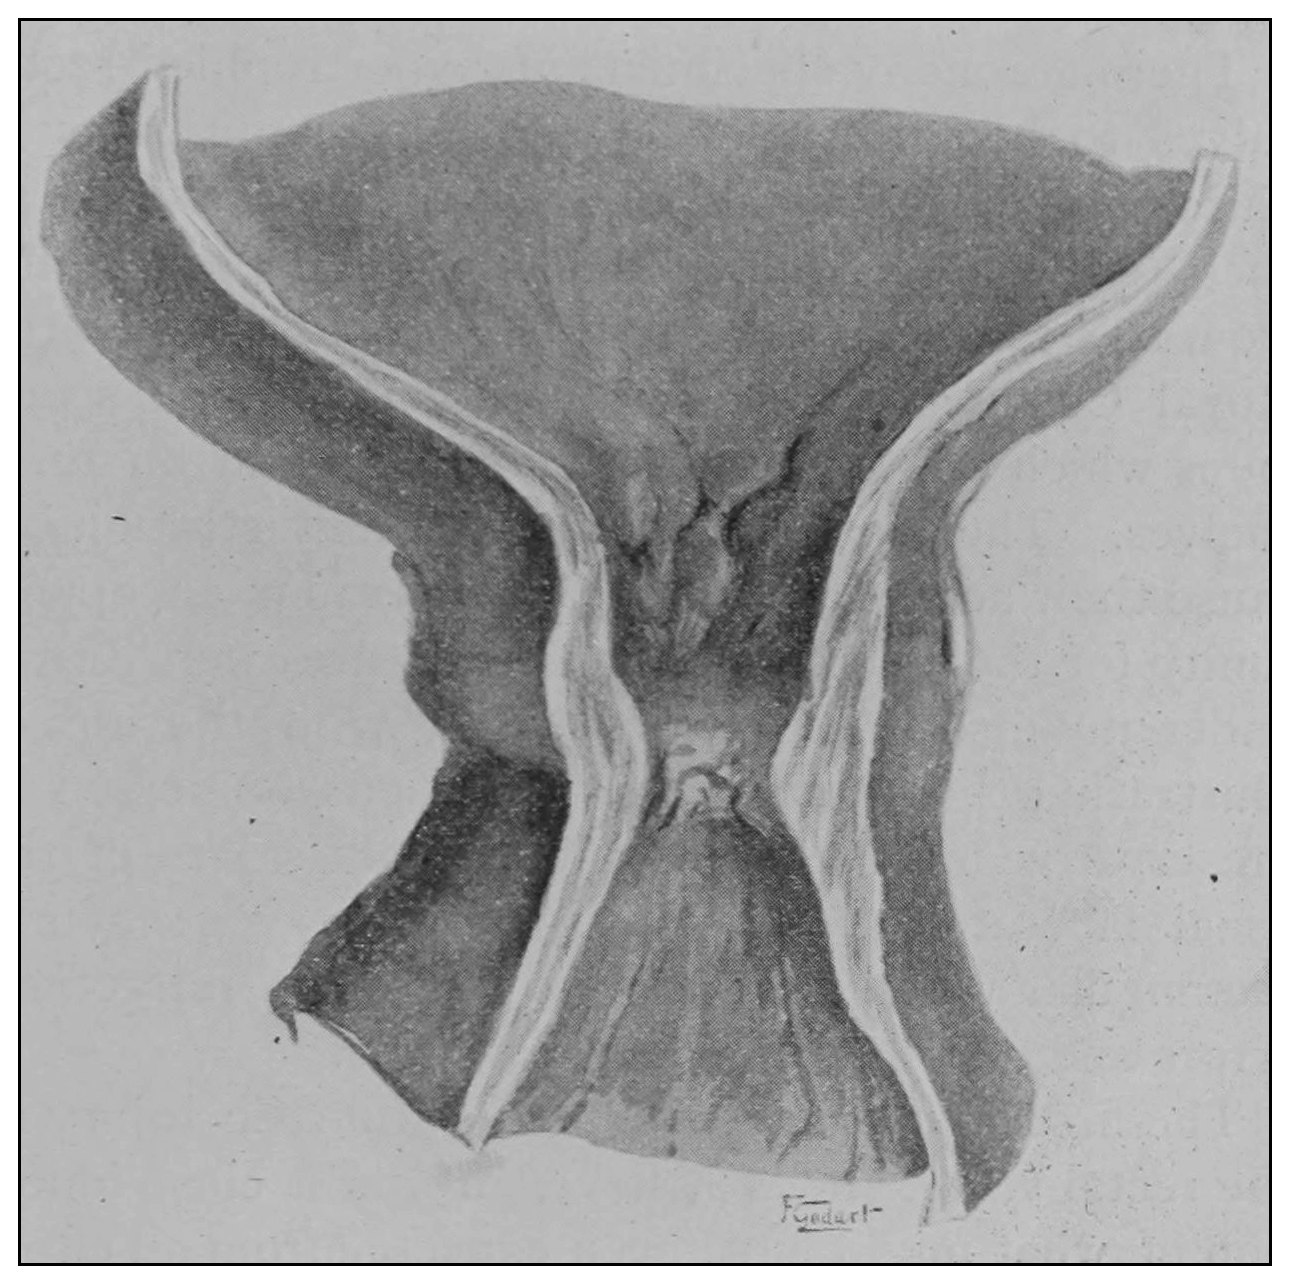

Velpeau supported Nelaton’s claim for the superior sphincter by removing the rectum and turning it inside out, so that its mucous membrane was external, and then by inflation demonstrated a marked constriction on the now external surface, which was distinctly claimed to be nothing other than a muscular band. It is not difficult to understand how the true valve within the normally situated gut would appear as a constricting band when the rectum is removed and turned in the manner described.

The photographic reproductions here published are documentary evidence of the existence of the obstructions under discussion. The sketch, Fig. 33, which was drawn from the valve while under the microscopic lens, exhibits the character of these obstructions and proves it that of a typic anatomic valve, and the absence of permanent bands of any other character in this organ is evidence that the semilunar valves and the so-called plica transversalis recti, Falten des Rectums, sphincter ani tertius, superior sphincter, and detrusor fecium muscles are one and the same thing and this thing is essentially a valve. It is most prominent when the gut is most distended.